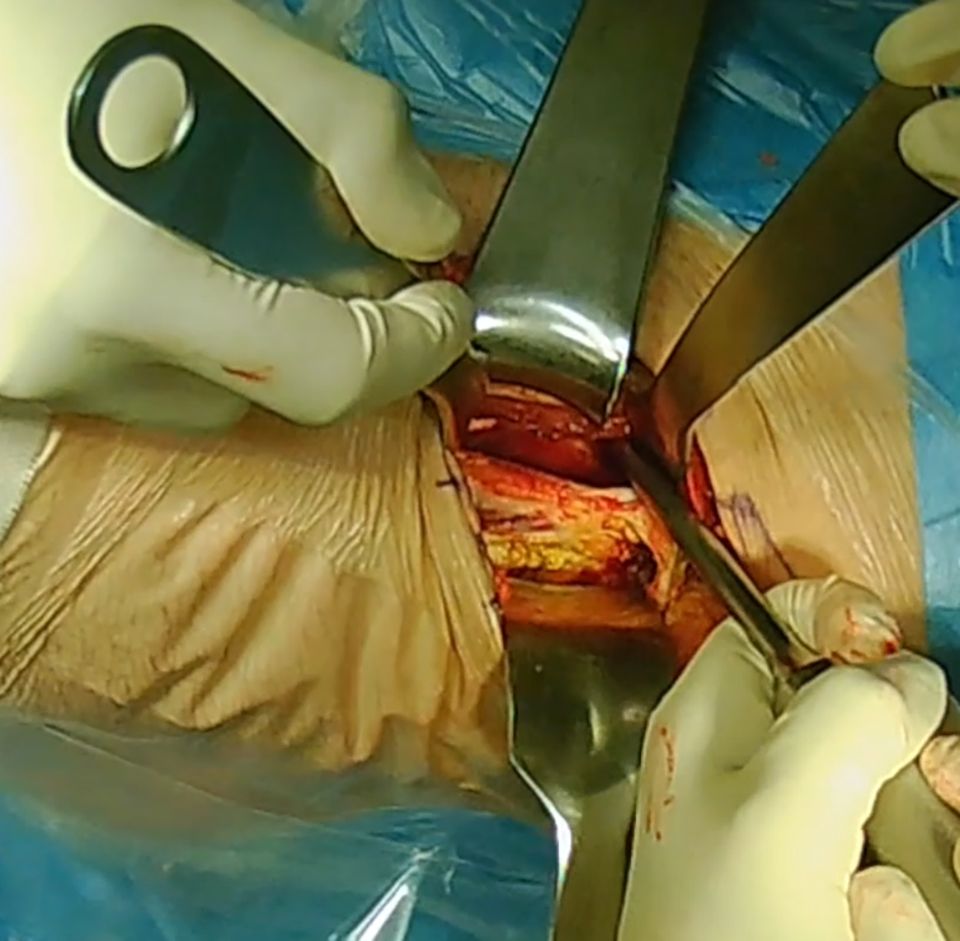

If this targeted ROM is not achieved, and the acetabular reorientation is correct an additional head-neck offset correction has to be performed. This offset correction is done via a classical direct anterior approach (Smith-Peterson interval) utilizing the interval medial of the tensor and lateral of the rectus and the sartorius muscle. The intervall between the M. sartorious and the M. tensor fascia latae (TFL) is bluntly dissected and two blunt curved Hohmann retractors are inserted to expose the capsule of the hip joint. The proximal insertion of the M. rectus femoris is bluntly liberated with a gauze-covered Cobb-raspatorium. Placement of a broad Hohmann retractor on the anterior acetabular column under the proximal insertion of the M. rectus femoris. T-shaped capsulotomy. The medial aspect of the capsulotomy should occur under visualization to avoid accidental damage to the labrum. Intracapsular placement of both blunt Hohmann retractors above and below the femoral neck (Fig 17).

Now remodulation of the femoral asphericity with a high-speed burr can be performed. The remodulation should extend right up to the acetabular labrum, without touching or damaging the labrum. Mobilization of the leg to visualize the hip joint and control the impingement-free range of motion. The minimum acceptable range of motion is 120° of flexion and 30° of internal rotation under simultaneous 90° of flexion. Radiographic control: A complete removal of the femoral asphericity is achieved (Fig 18).